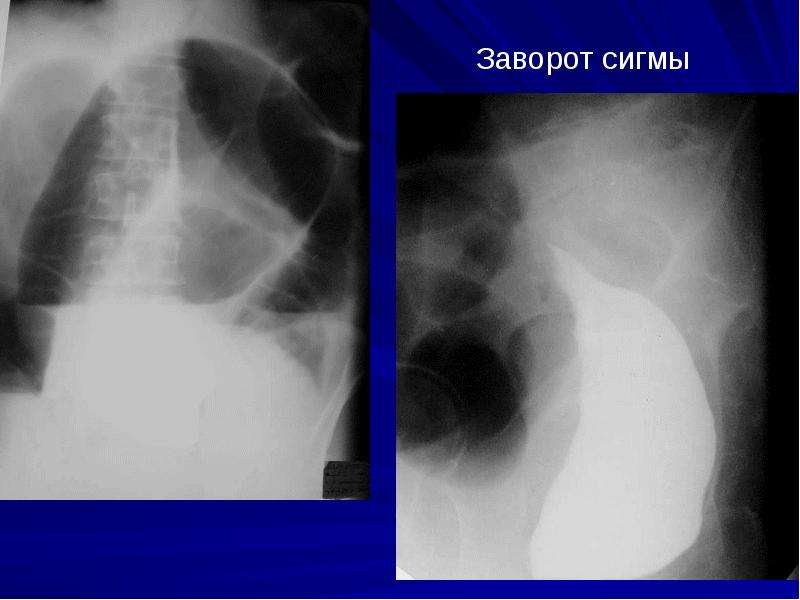

Иллюстрации и информация о симптомах острого кишечного непроходимости